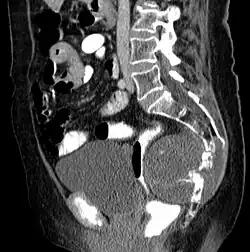

Chordome sind langsam und destruktiv wachsende Tumoren der Wirbelsäule und der Schädelbasis, die in etwa 10 % der Fälle metastasieren.

Chordome werden manchmal zu den Knochentumoren gezählt, obwohl sie nicht aus Knochengewebe stammen, sondern aus Resten der Chorda dorsalis (Notochordoa) an den Enden der Wirbelsäule. Damit lassen sich auch ihre Hauptlokalisationen, nämlich Schädelbasis und Steißbein, erklären. Die ICD-O-3 klassifiziert sie unter die Sonstigen Tumoren des Nervensystems (Nr. 937).

Symptome entstehen besonders durch Druck auf Nerven durch den Tumor, was allgemein zu Schmerzen und Nervenausfällen führen kann. Chordome im Bereich der Schädelbasis führen so zu Kopf- und Nackenschmerzen, Diplopie und weiteren Hirnnervenausfällen[1].